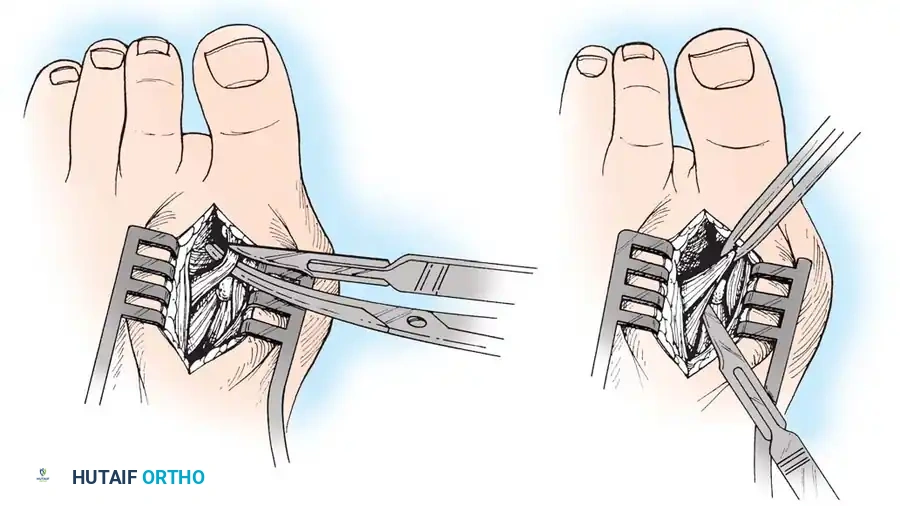

• The main portion of the adductor tendon inserts into the base of the proximal phalanx just plantar to the longitudinal axis of the phalanx. It also has a smaller insertion, along with the lateral head of the fl exor hallucis brevis muscle, into the fi bular sesamoid. The simplest technique to identify the insertion of the adductor hallucis tendon is to place a small, pointed, curved hemostat on the dorsolateral base of the proximal phalanx, slide it fi rmly plantarward, and lift the hemostat dorsally and laterally; the tip of the instrument usually rests in the axilla of the insertion of the adductor tendon (Fig. 78-19A). This is comparable to securing the iliopsoas tendon for tenotomy at the lesser trochanter.

• When the primary insertion is released, grasp the tendon with forceps or a hemostat, and, with traction, displace it dorsally and laterally toward the second metatarsal so that further dissection is on the medial side of the adductor or push the sesamoid sling laterally through the previously placed medial incision to aid exposure.

• While spreading the fi rst and second metatarsal heads with a small Inge retractor, heavy-duty two-tooth retractors, or a Weitlaner retractor, hold the adductor tendon under tension, which facilitates exposure. The lateral head of the fl exor hallucis brevis muscle, the lateral border of the fi bular sesamoid, and the slip of the adductor tendon (confl uent with the lateral head of the fl exor hallucis brevis muscle) come into view in the depths of the wound.

• All attachments of the adductor into its conjoined insertion with the lateral head of the fl exor hallucis brevis muscle into the fi bular sesamoid must be severed; with traction on the adductor, it freely and independently moves without tethering the fi bular sesamoid (Fig. 78-19B).

• This deep transverse intermetatarsal ligament, which lies just plantar to the adductor, may be released by the incision along the lateral border of the sesamoid. If not, release this ligament, carefully preserving the neurovascular bundle immediately beneath it, and incise the lateral capsule. Mann emphasized that release of the deep transverse metatarsal ligament endangers the neurovascular bundle to the fi rst web space, which lies immediately beneath this ligament. Sliding a small Freer elevator between this ligament and the neurovascular bundle would protect the latter structures.

Fig. 78-19 Modifi ed McBride procedure. A and B, Adductor hallucis is exposed and released (see text).